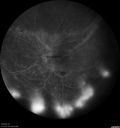

Grade 4 hypertensive retinopathy452 views55 year old man Hhe did have headaches a few weeks ago and also some nausea and vomiting. He noticed for a few weeks the vision in the left eye was blurred and that the vision in the left eye is dark.

VA OD: Dcc20/20

VA OS: Dcc20/100-1

He was admitted directly to ICU for blood pressure control (290 / 170 mmHg)

3 weeks later his VA increased to 20/20 OD, 20/32 OSJan 29, 2019